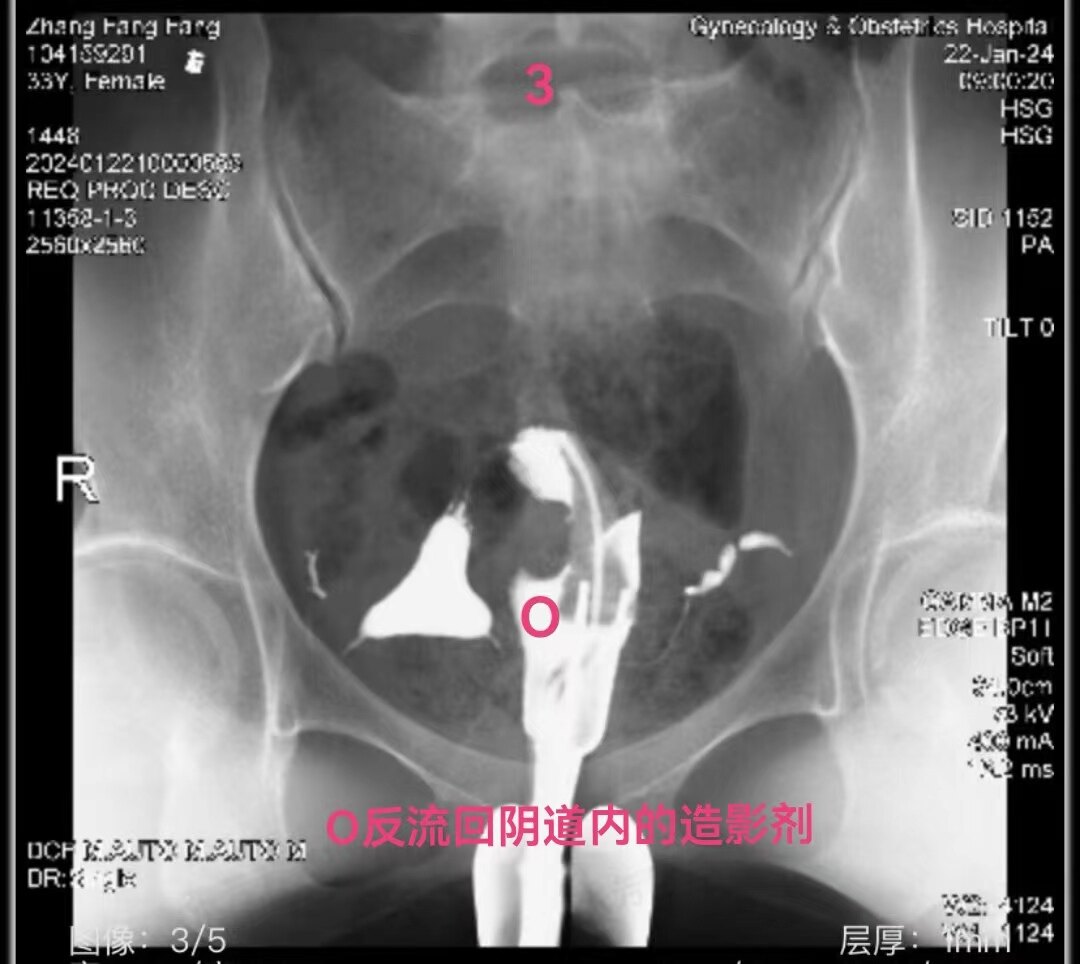

3.jpg

左侧输卵管显影至壶腹部远端,右侧输卵管显影至壶腹部近段。造影剂返回到阴道